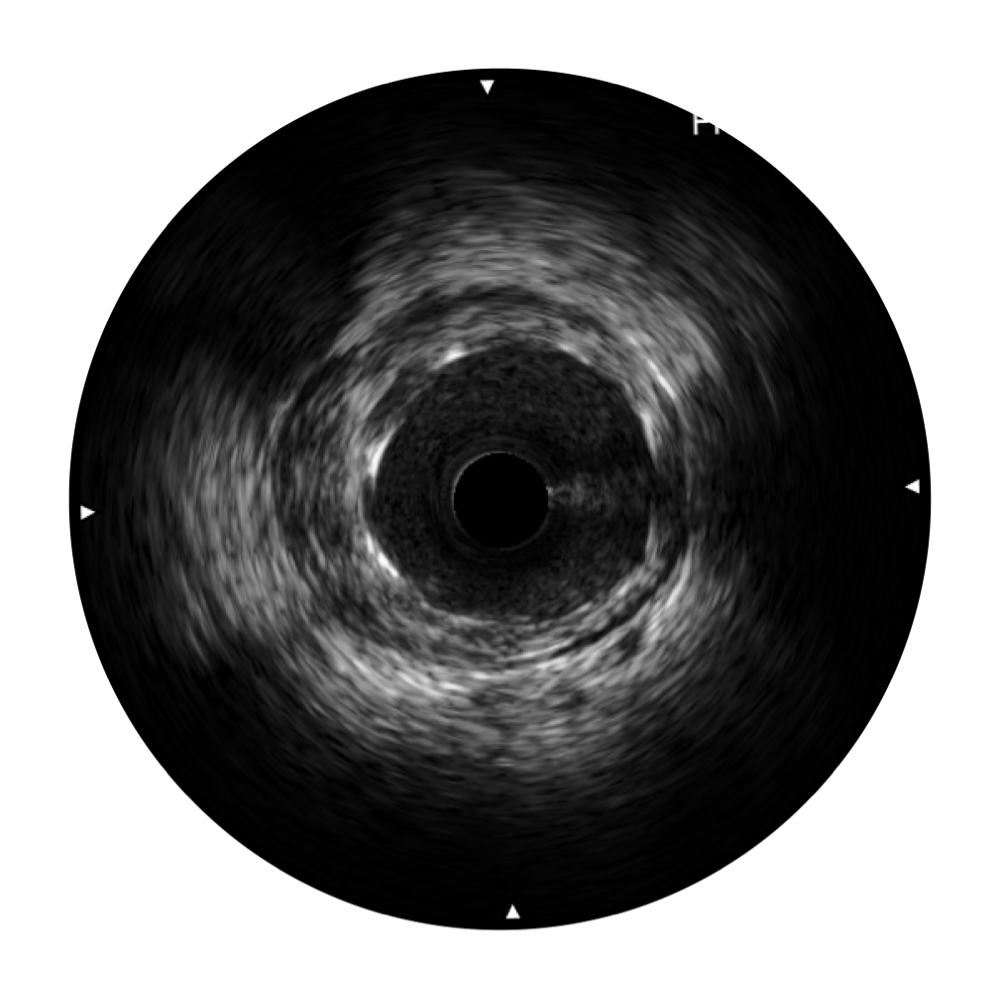

• 美狮贵宾会官网宽频IVUS图像

• 传统IVUS图像

对比传统IVUS导管成像,美狮贵宾会官网宽频IVUS图像的近场支架梁显影更细腻,远场中膜外血管仍清晰可辨,兼顾远中近,兼顾分辨力与穿透深度